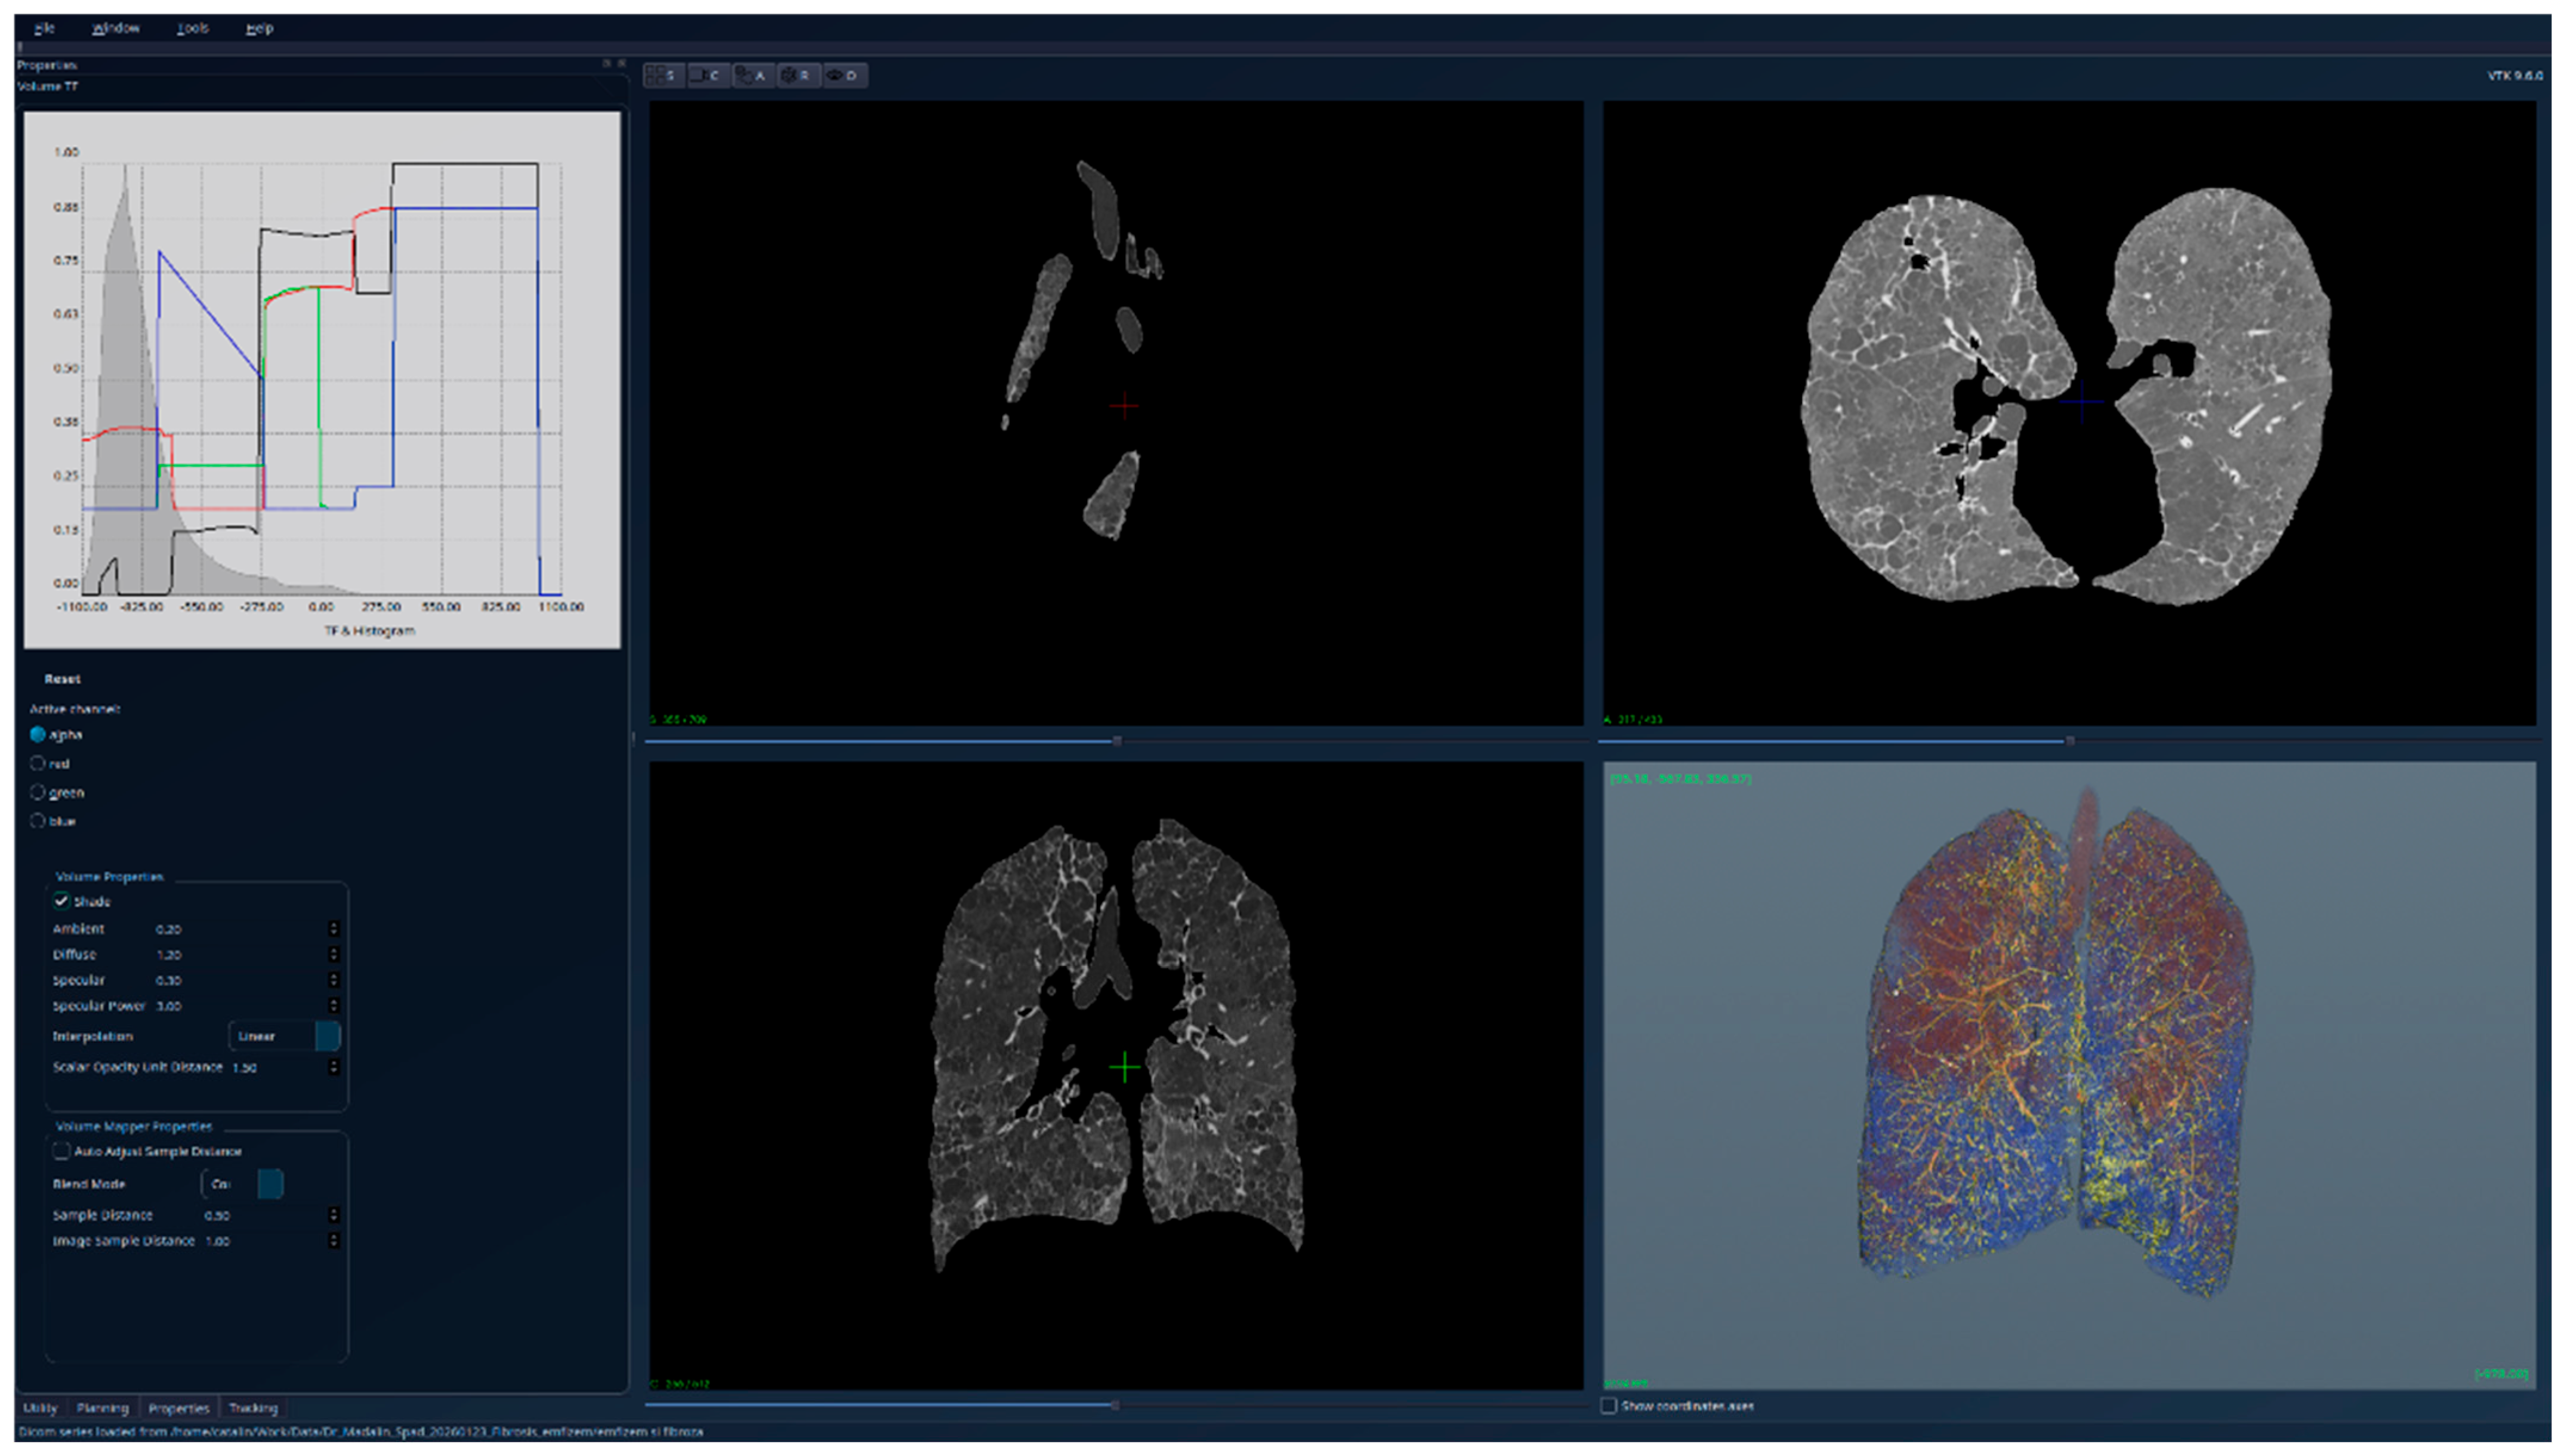

3. Results

| Theoretical lungs model | 512 × 512 × 512 | 0.5 × 0.5 × 0.5 | 5227 |